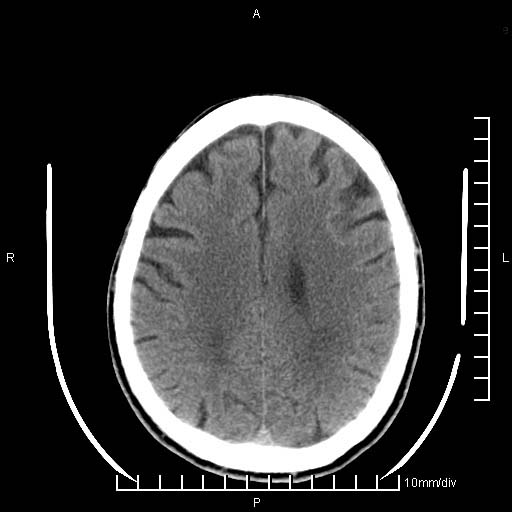

临床以双下肢浮肿,疼痛收治,无明显神经系统症状,既往无梗塞,出血病史。左颞叶见低密度灶,考虑什么?

考虑左侧颞叶脑软化灶。

无强化 无占位 软化灶吧

无强化、 无占位、局部脑沟增宽, 软化灶吧。